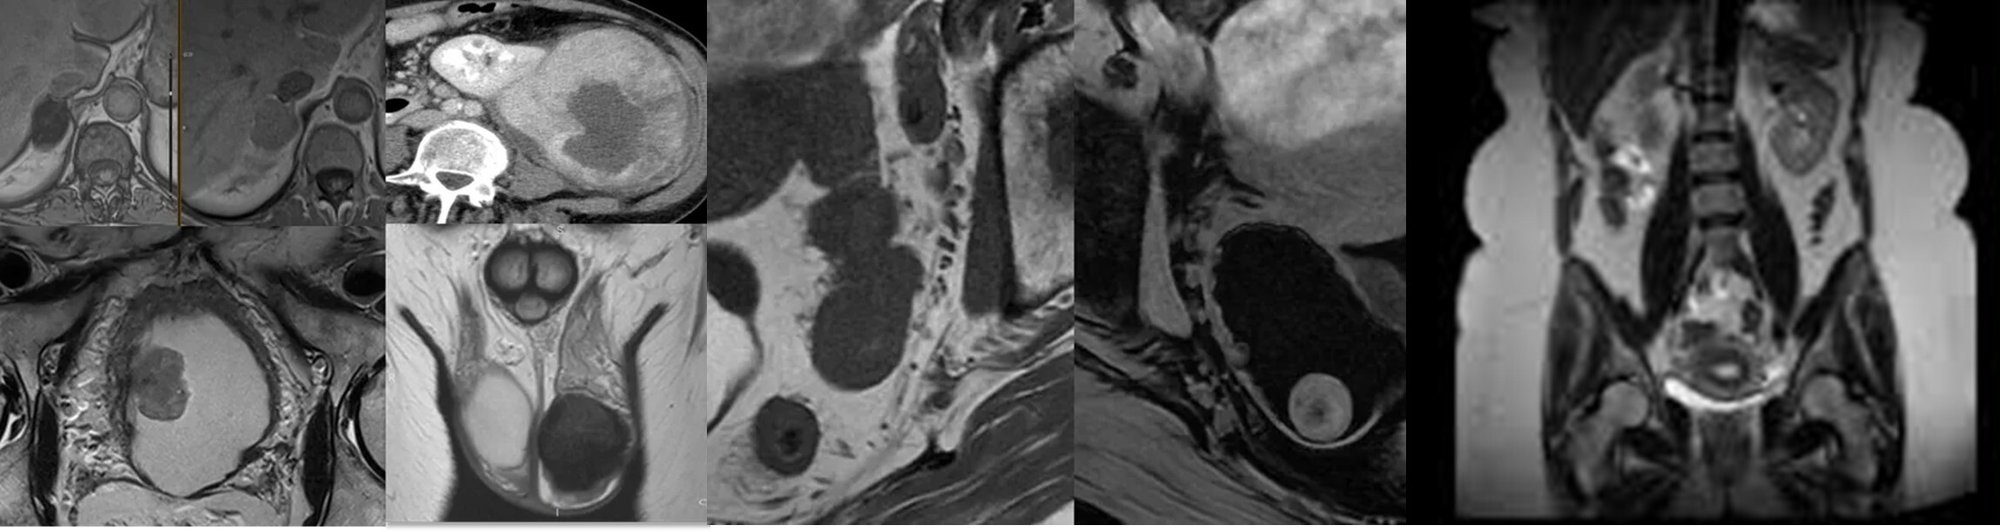

An interactive, case-based virtual course on Collective Minds, led by expert speakers covering a broad range of Uro- and Gynae pathologies. Designed for radiology trainees, this focused programme will deepen your subspecialty knowledge and build confidence through real-world, specialist-led teaching.